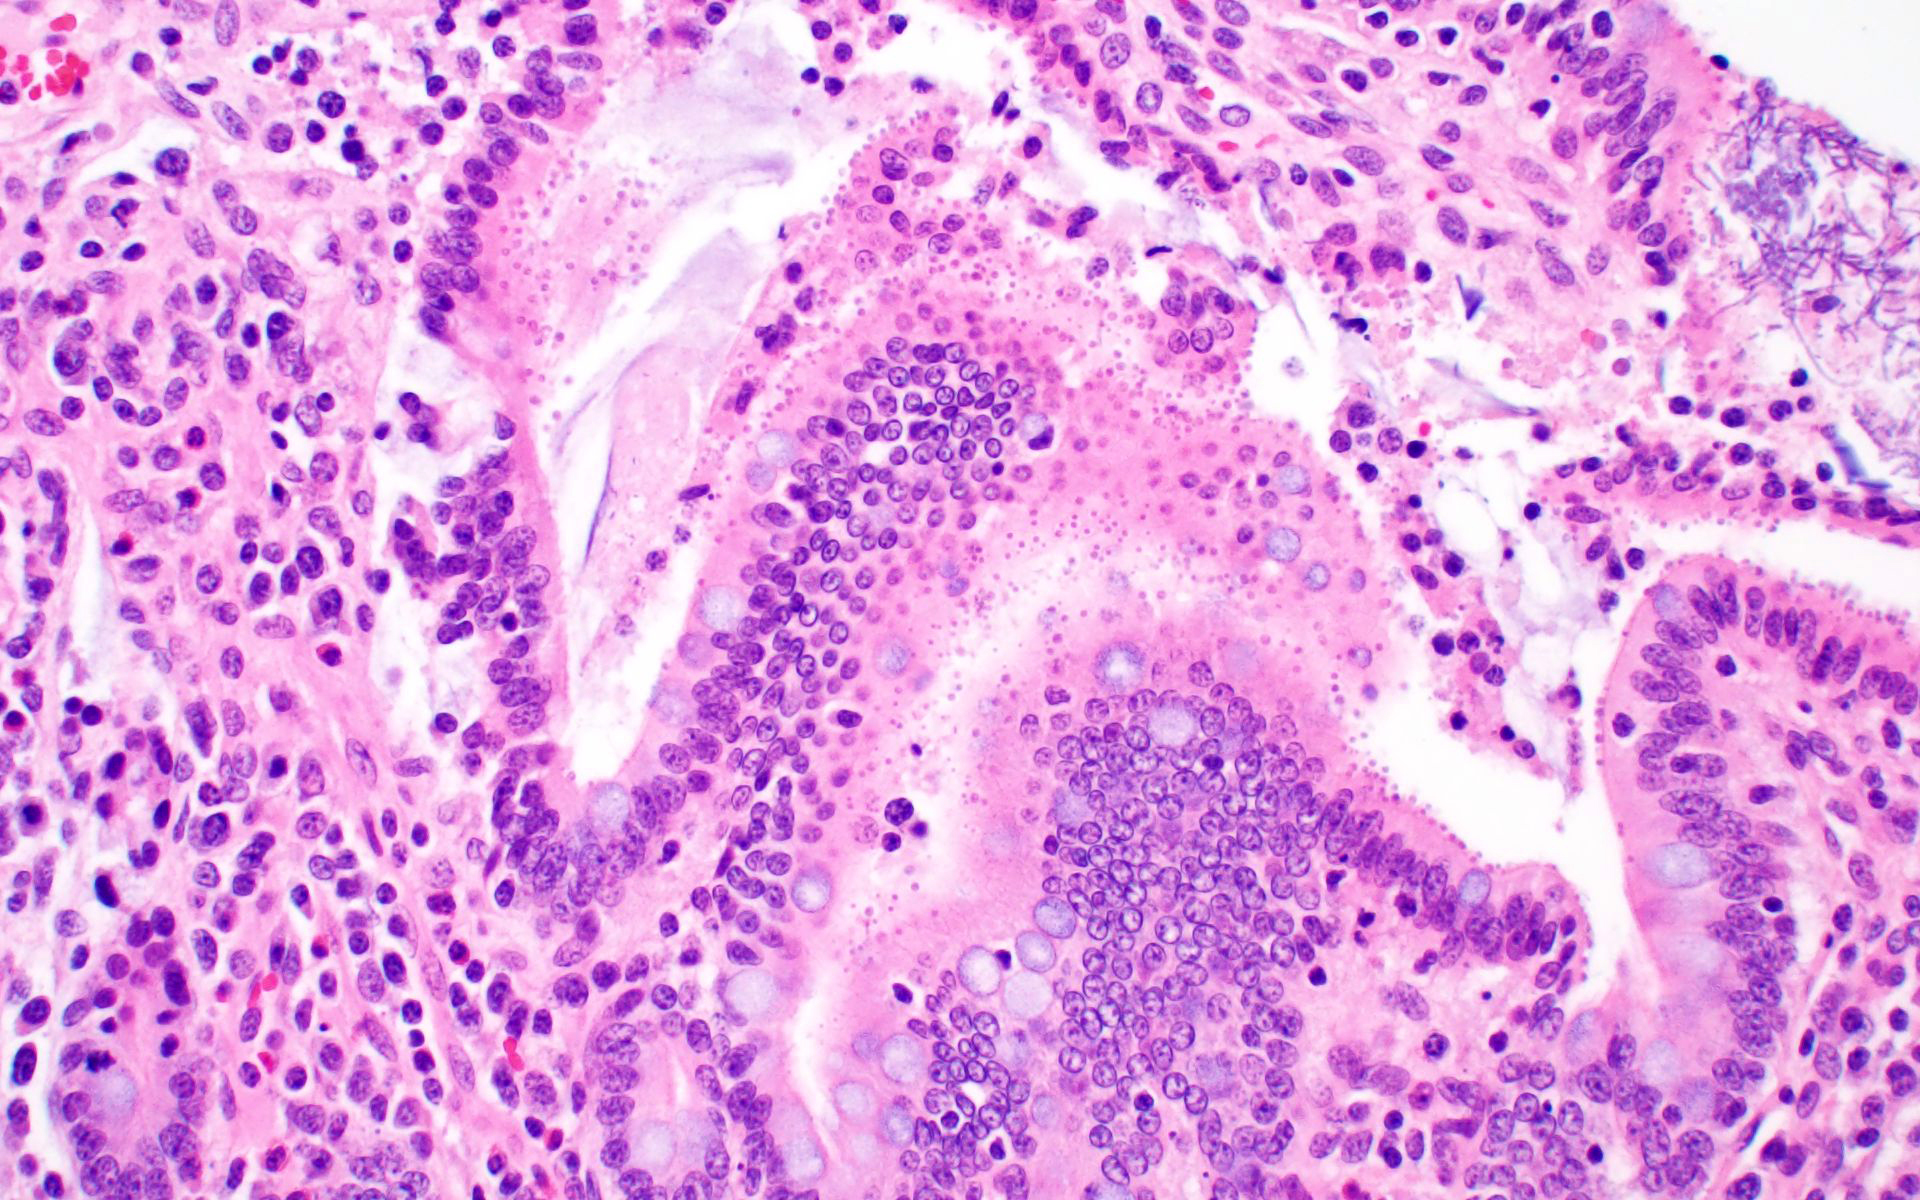

Ileum: In several sections, there is moderate multifocal blunting and fusion of villi with a crypt: villus ratio of 1:1. Apical enterocytes are often moderately attenuated with loss of the brush border and reduced apical cytoplasm. In some sections, these cells have a profound number of intracellular but extracytoplasmic 1-2 um circular eosinophilic apicomplexan organisms with 0.5 um basophilic nuclei (Cryptosporidium sp.). In other sections, these cells contain numerous larger apicomplexans with varied life-stages apparent including: 10 x 5 um curvilinear binucleate meronts (type I meronts), 4 x 12 um curvilinear uninucleate merozoites (type I merozoites), 9 x 6 um ovoid multinucleate meronts (type II meronts), multiple 3 x 12 um curvilinear uninucleate merozoites joined at their base by a residual body (type II merozoites), a 12um diameter circular lightly basophilic microgamont filled with numerous peripheral uninucleate deeply basophilic microgametes, or a 18 um diameter circular lightly basophilic macrogamont with a 8 um granular circular nucleus (macrogamont) (Cystoisospora suis). Rare crypts are ectatic, lined by moderately flattened, attenuated epithelium, and filled with cellular and karyorrhectic debris admixed with rare degenerate neutrophils (crypt abscesses). The associated lamina propria is often infiltrated by numerous eosinophils admixed with a few neutrophils. In one section, there is profound necrosis in Peyer’s patches, characterized by abundant karyorrhectic and cellular debris admixed with rare neutrophils, that often obscures typical follicular architecture. Similar changes are occasionally present in the overlying lamina propria, with marked lymphocytolysis and loss of proprial architecture. Vascular structures in all tunics are moderately congested, and macrophages occasionally aggregate around medium-caliber vessels in the submucosa.Spiral Colon: In both sections, there is moderate multifocal ulceration of the colonic mucosa characterized by loss of apical colonocytes with abundant cellular and karyorrhectic debris admixed with minimal fibrin and extravasated erythrocytes adhered to the exposed lamina propria. Adjacent colonocytes are often flattened, irregularly spaced, with reduced apical cytoplasm (attenuation). The associated lamina propria is often infiltrated by neutrophils and eosinophils admixed with necrotic debris and a few macrophages. Crypts within these areas are often ectatic, lined by mildly attenuated epithelium, and filled with either cellular and karyorrhectic debris admixed with degenerate neutrophils (crypt abscesses) or numerous eosinophils. Several other crypts are filled with up to 15 5 x 7 um pyriform to crescent-shaped protozoa with lightly basophilic cytoplasm and a faint nucleus (Suspect Trichomonads). The colonic lumen contains abundant cellular debris admixed with numerous colonies of basophilic bacteria with morphology ranging from coccoid to bacillary to filamentous, as well as rare 80 um circular flagellated protozoa with a prominent bean-shaped nucleus and a large cytoplasmic vacuole and abundant phagocytosed cellular debris (Suspect Balantidium coli). The submucosa is multifocally infiltrated by numerous macrophages admixed with lymphocytes and a small amount of karyorrhectic debris and these cells often aggregate around medium to large caliber vessels. Multifocally the cortical and medullary architecture of the mesenteric lymph node is effaced by abundant cellular and karyorrhectic debris (lymphocytolysis) admixed with rare infiltrating neutrophils and macrophages.

Ileum and colon (mediastinal lymph node, Peyer’s patches, and lamina propria): Lymphoid necrosis, multifocal, profound, subacute.Ileum: Atrophic enteritis, necrosuppurative and eosinophilic segmental, marked, subacute, with crypt abscesses and numerous intralesional apicomplexans with morphology consistent with Cryptosporidium spp. and Cystoisospora suis

This is great example of a real-world production animal diagnostic case. It’s also a great reminder to look for a primary etiology when there are multiple organisms/changes present in a piece of tissue that aren’t typically seen together. Cryptosporidium suis and scrofarum are present in many commercial pigs but typically do not cause clinical disease and are generally not histologically apparent.8,13 The presence of such profound quantities of Cryptosporidium spp. in this case suggests primary immune suppression. The larger apicomplexan present in this slide has life stages that are morphologically consistent with Cystoisospora suis. While this organism can act as a primary enteric pathogen in pigs, it is also present at low levels in many commercial swine post-weaning without causing clinical disease, often with few if any histologically apparent life-stages. The presence of both types of meronts, both types of merozoites, as well as microgamonts and macrogamonts in a single section of tissue is unusual and also suggests that primary immune suppression may be at play. Lindsay et al. did a great job describing these life stages in a in 1980 Journal of Parasitology paper.7 The moderate ulcerative colitis in this animal is typical of a Salmonella spp. It’s also common to have Balantidium coli find their way into these colonic lesions, often phagocytosing necrotic debris.9,13 The pyriform organisms in the colonic crypts are morphologically consistent with trichomonads. Tetratrichomanas foetus, suis,buttreyi, and Pentatrichomonas hominis have all been described as inhabitants of the porcine digestive tract. Others are likely present in pigs, and there have been increased efforts, especially in China, to better characterize these organisms.6 They are commonly seen in higher numbers in porcine colonic crypts during disease or dysbiosis.PCV-2 parasitizes lymphocytes and is a common cause of immune suppression in commercial pigs. However, this virus typically causes lymphoid depletion with granulomatous inflammation and rarely intracytoplasmic botryoid inclusion bodies. PCV-2/3 differential PCR was negative in this animal. The massive amount of karyorrhectic debris in the lymphoid tissue is more in line with PRRSV infection, which was detected at a very low CT in lung, and colocalized to the lesioned enteric lymphoid tissue by IHC. PRRSV is a member of the family Arteriviridae, which together with Coronaviridae, Roniviridae, and Mesonoviridae form the order Nidovirales, a contemporarily relevant viral order that has evolved a unique replication strategy utilizing discontinuous extension and a set of nested subgenomic mRNAs. The economic impact of PRRSV in the US is estimated to be $660 million annually, and a reasonable case could be made that this is the most economically important virus of any domestic species in the US.3 PRRSV replicates in macrophages and, to a lesser extent, dendritic cells. There was much historical controversy about the receptor utilized by this virus for cell entry. In a landmark paper, Prather et al. were able to demonstrate complete resistance to the virus by knocking out CD163 in commercial pigs with CRISPR/Cas9 methods.11 CD163 (HbSR) is a hemoglobin scavenger receptor that is expressed in cells of the monocyte-macrophage lineage.1 Currently, CD163 knock-out pigs are working their way through the federal regulatory system, with the genetics company involved hoping to market a completely PRRSV resistant animal. This may have huge economic implications given the limited success of commercial vaccines against this phylogenetically diverse virus. While this virus is classically associated with interstitial pneumonia with intralesional “necrotic macrophages”, it’s a systemic pathogen that can infect macrophages in any body system, especially lymphoid tissue. The terms “necrotic macrophages” and “lymphoid necrosis” are somewhat controversial in PRRSV infection. An early paper utilizing tunnel assays, demonstrated widespread apoptosis of noninfected cells in the lung, testes, and lymphoid tissue, giving rise to the idea of “bystander-apoptosis” involvement in the pathogenesis of this virus.10 Subsequent papers further characterizing the involvement of intrinsic/extrinsic/other apoptotic pathways in infected and uninfected cells are conflicting.2 At the very least it can be stated that much of the cell death in a PRRSV infection occurs in uninfected cells, and a significant proportion of those cells are likely apoptotic as opposed to necrotic.